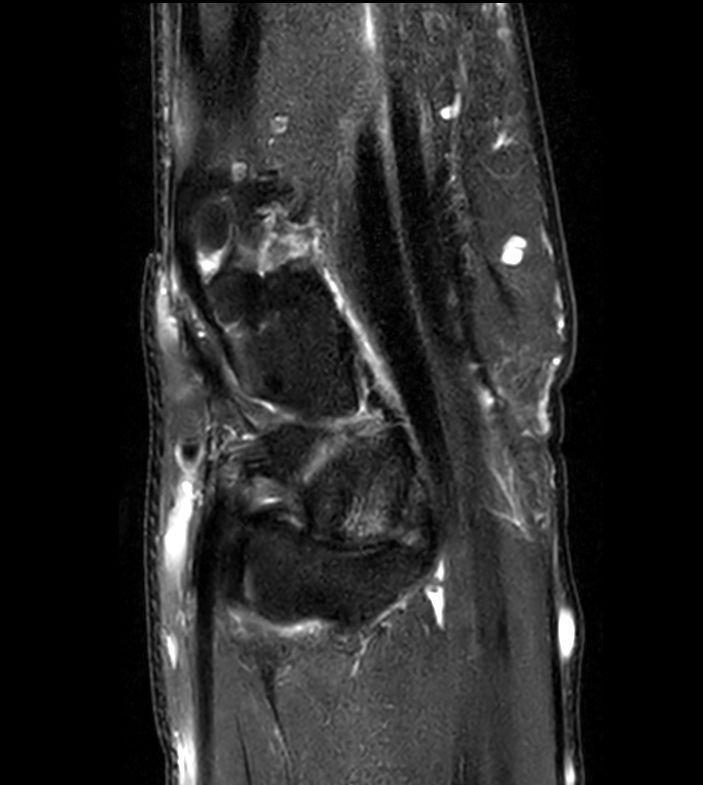

Off-center imaging of the Wrist with the dS HandWrist 16ch coil. Compressed SENSE is used to speed up the entire exam with virtually equal image quality.2.